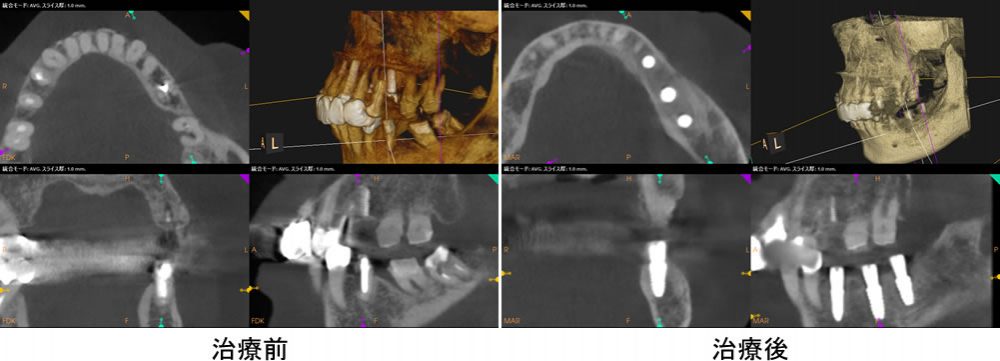

インプラント埋入前後のCT画像の比較

PRP(多血小板血漿)によって、かなりの骨が再生していることが分かります。